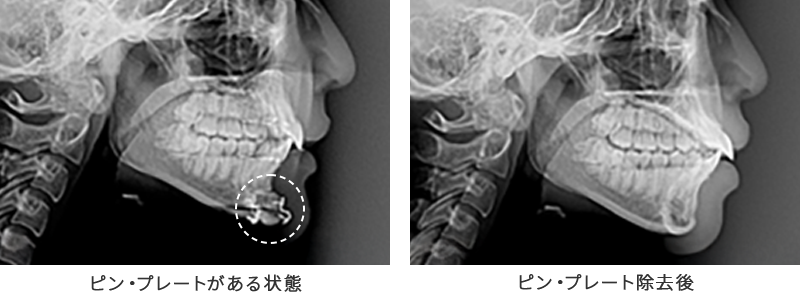

ルフォーやSSRO、オトガイ形成などの両顎手術や頬骨整形では、再配置した骨片がズレないように骨・皮膚・筋肉の適切な癒合を促進する目的で術中に医療用プレートやワイヤー、スクリュー(ピン・ネジ)を使用して固定作業を行います。

これらのプレート・ピンは体内に残ったままの状態でも問題はないのですが、患者様によっては「レントゲン検査などで映らないようにしたい」などの理由から抜去を希望されるケースがあります。ピン・プレート除去術は、このような輪郭手術で体内に挿入したプレートやピンなどを除去する手術で、当院では他院や海外(韓国など)で行った輪郭手術のプレート除去・ピン除去にも対応しています。